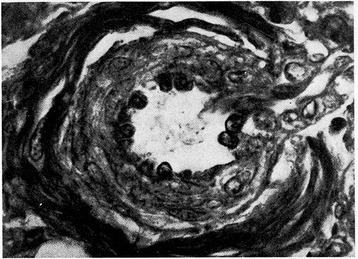

Figure 1.

Pulmonary arteriole from one-day-old infant. The medial muscle mass is conspicuous (Verhoeff’s and Van Gieson’s stains). From Naeye and Letts [20], Pediatrics 1962.